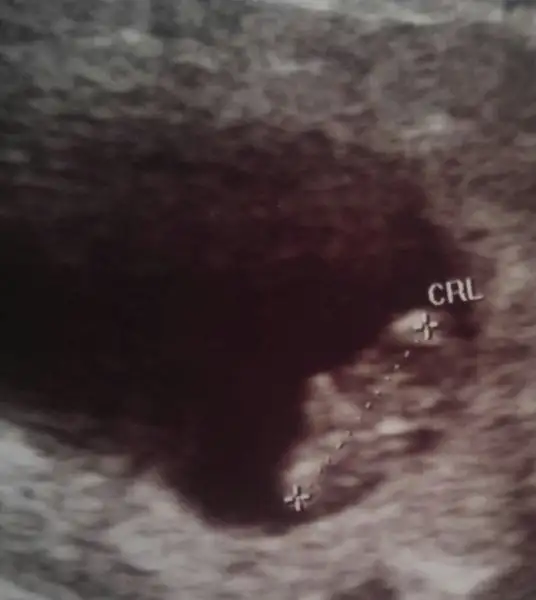

Geçmiş olsun canım yat dinlen bol bol kendini yormamaya çalış ilacıda kullan gönlünü ferah tutSabah gittim bebegimi gordum hareket ediyordu, kan dolasimi baslamis onuda gorduk. Kalbini dinledik 173. Doktor hersey yolunda dedi. Sevine sevine geldim. Herkes telefon etti sordu herkese iyi cok sukur dedim. Eve geldim yapis yapis birsey hissettim baktim akintinin icinde kan vardi. Hemen kendi doktoruma sordum beklenmeyen birsey ben hastanede degilim ama hemen gel biri baksin dedi. En yakin hastaneye gittim vajinal bakti bebegi gordum kalp atisini duydum kese cevresinde birsey yok dedi. Progestron verdi dinlen dedi. Sanki yarim saat icinde yaslandim. Elim ayagim titredi. Allahim bebeklerimizi korusun. Hepimiz icin hayirlisi olsun.